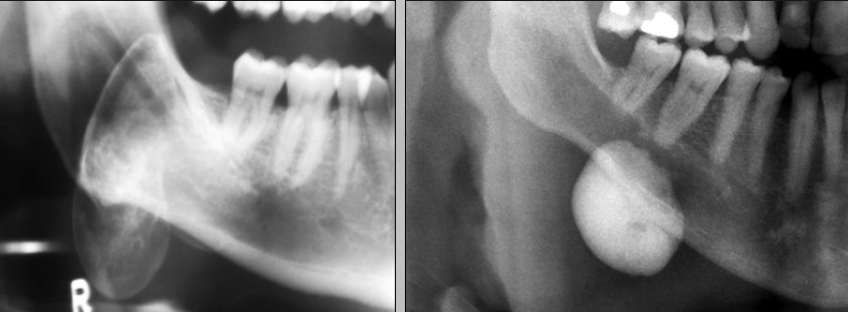

Colorectal Polyps seen in Gardner Syndrome

Pano of patient with gardner syndrome

Pano of patient with Gardner Syndrome has supernumerary teeth

Seen in 20% of patients and cleidocranial dysplasia (more common)